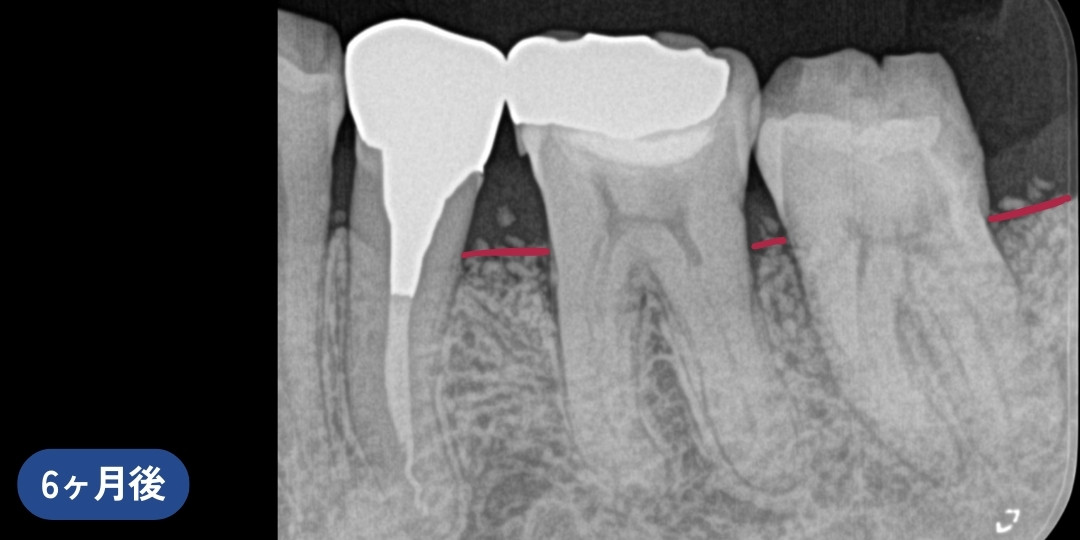

リグロスを用いた歯周組織再生療法後、骨の再生が認められました。※写真内赤線箇所

期間6ヶ月

費用歯周基本治療、リグロスを用いる歯周組織再生療法

2~3万円